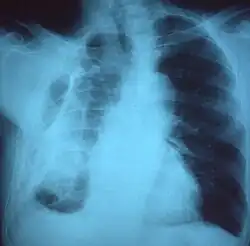

If a fibrothorax is severe, the thickening may restrict the lung on the affected side causing a loss of lung volume.[7] Additionally, the mediastinum may be physically shifted toward the affected side.[3] A reduction in the size of one side of the chest (hemithorax) on an X-ray or CT scan of the chest suggests chronic scarring.[6] Signs of the underlying disease causing the fibrothorax are also occasionally seen on the X-ray.[6] A CT scan may show features similar to those seen on a plain X-ray.[7] Lung function testing typically demonstrates findings consistent with restrictive lung disease.[6]

Extensive left-sided fibrothorax -

Chest radiograph displaying inhomogeneous opacification of the left half of the chest that is fibrothorax -